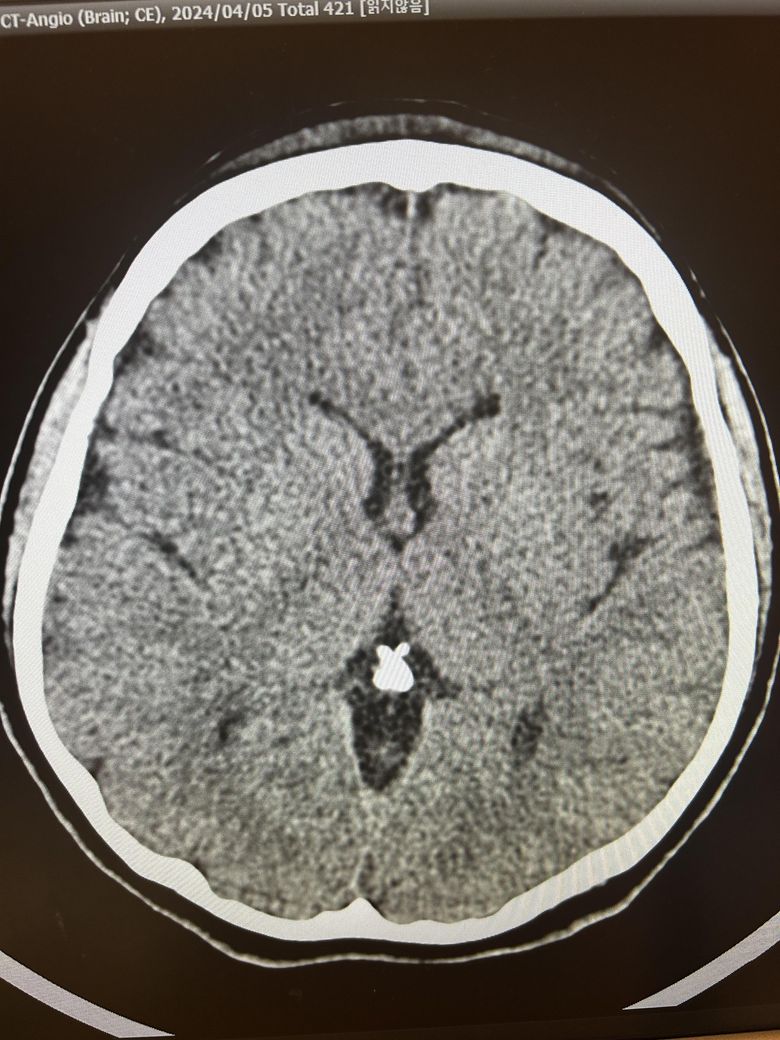

두통과 목뻐근함이 일주일째 심해서 뇌ct검사를 했습니다.

영상은 이렇게 보이는데 어떻게 의심되시나요?

석회화랑 다른것도 보이시나요?